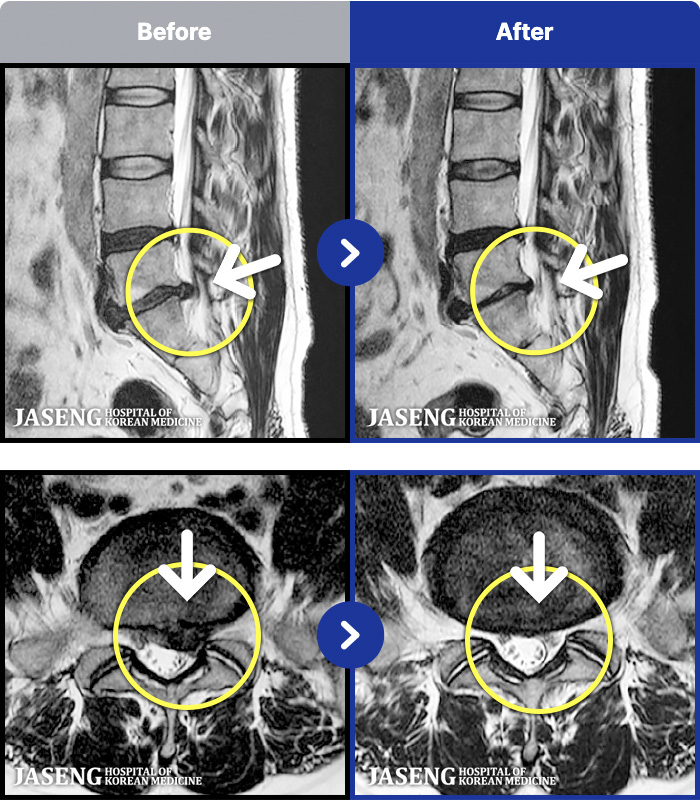

[뱸] 19.11.28~25.05.06

ȯںп Ǹ ǿ ԿǾ, ο ġ ۿ Ƿ ġḦ Ͻñ ٶϴ.